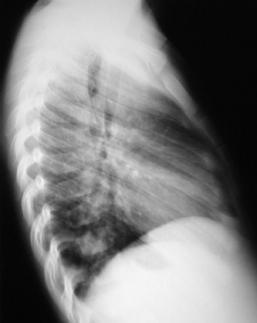

Radiografía del tórax

Rx. Tórax LI. Radiopacidad peritraqueal redondeada y lobulada prominente en mediastino anterior y superior que incrementa el contraste de radiotrasperencia traqueal, observándose estenosis en su porción distal.